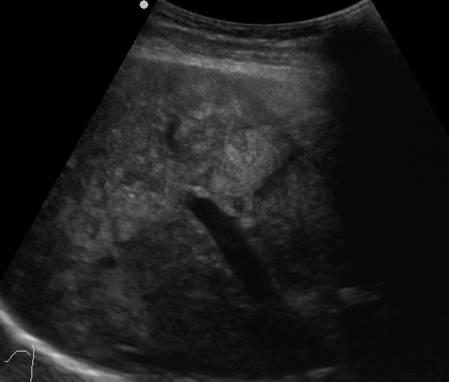

Gan nhiễm mỡ

» Thông tin: Nữ giới – 40 tuổi.

» Lâm sàng: Kiểm tra sức khỏe.